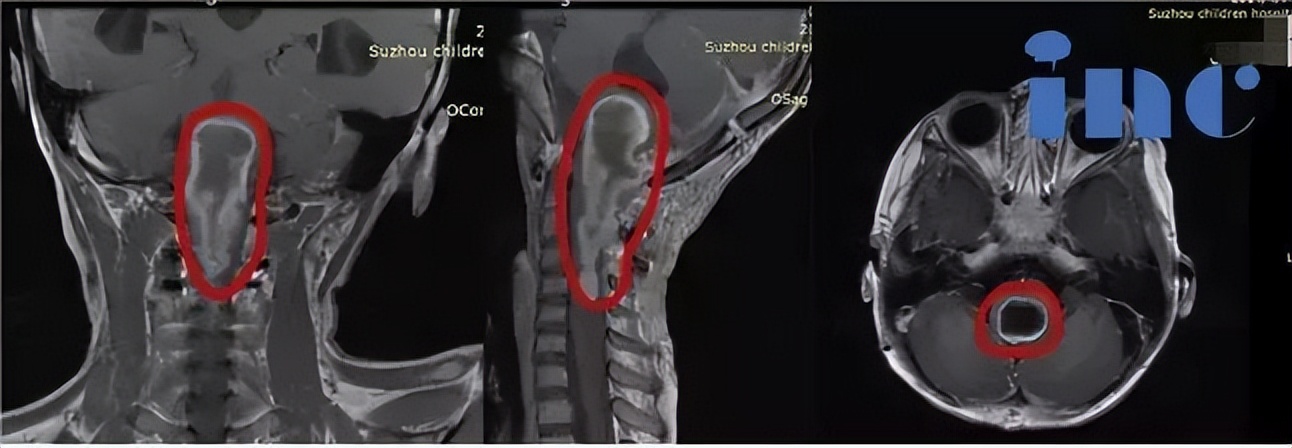

6岁女孩脑干延髓巨大胶质瘤获95%以上切除

患者情况:6岁女孩,脑干胶质瘤,肿瘤位于脑干延髓一直延伸至颈5节段脊髓,国内医生均表示风险太大,无手术机会。

治疗过程:2019年在INC德国巴特朗菲教授国内手术示范期间接受这位德国专家主刀手术,肿瘤切除率高达95%以上。

术后情况:术后ICU留观1天,神志清楚,完全自主呼吸,拔除插管,生命体征平稳,转入普通病房。患儿右侧肢体活动度、肌力较术前明显好转。术后1周,患者下地自行行走,无手术并发症出现。术后3周出院。术后患儿一直坚持在家做康复训练,术后10个月,患儿生活学习都与正常孩子一样,生长发育没受影响。